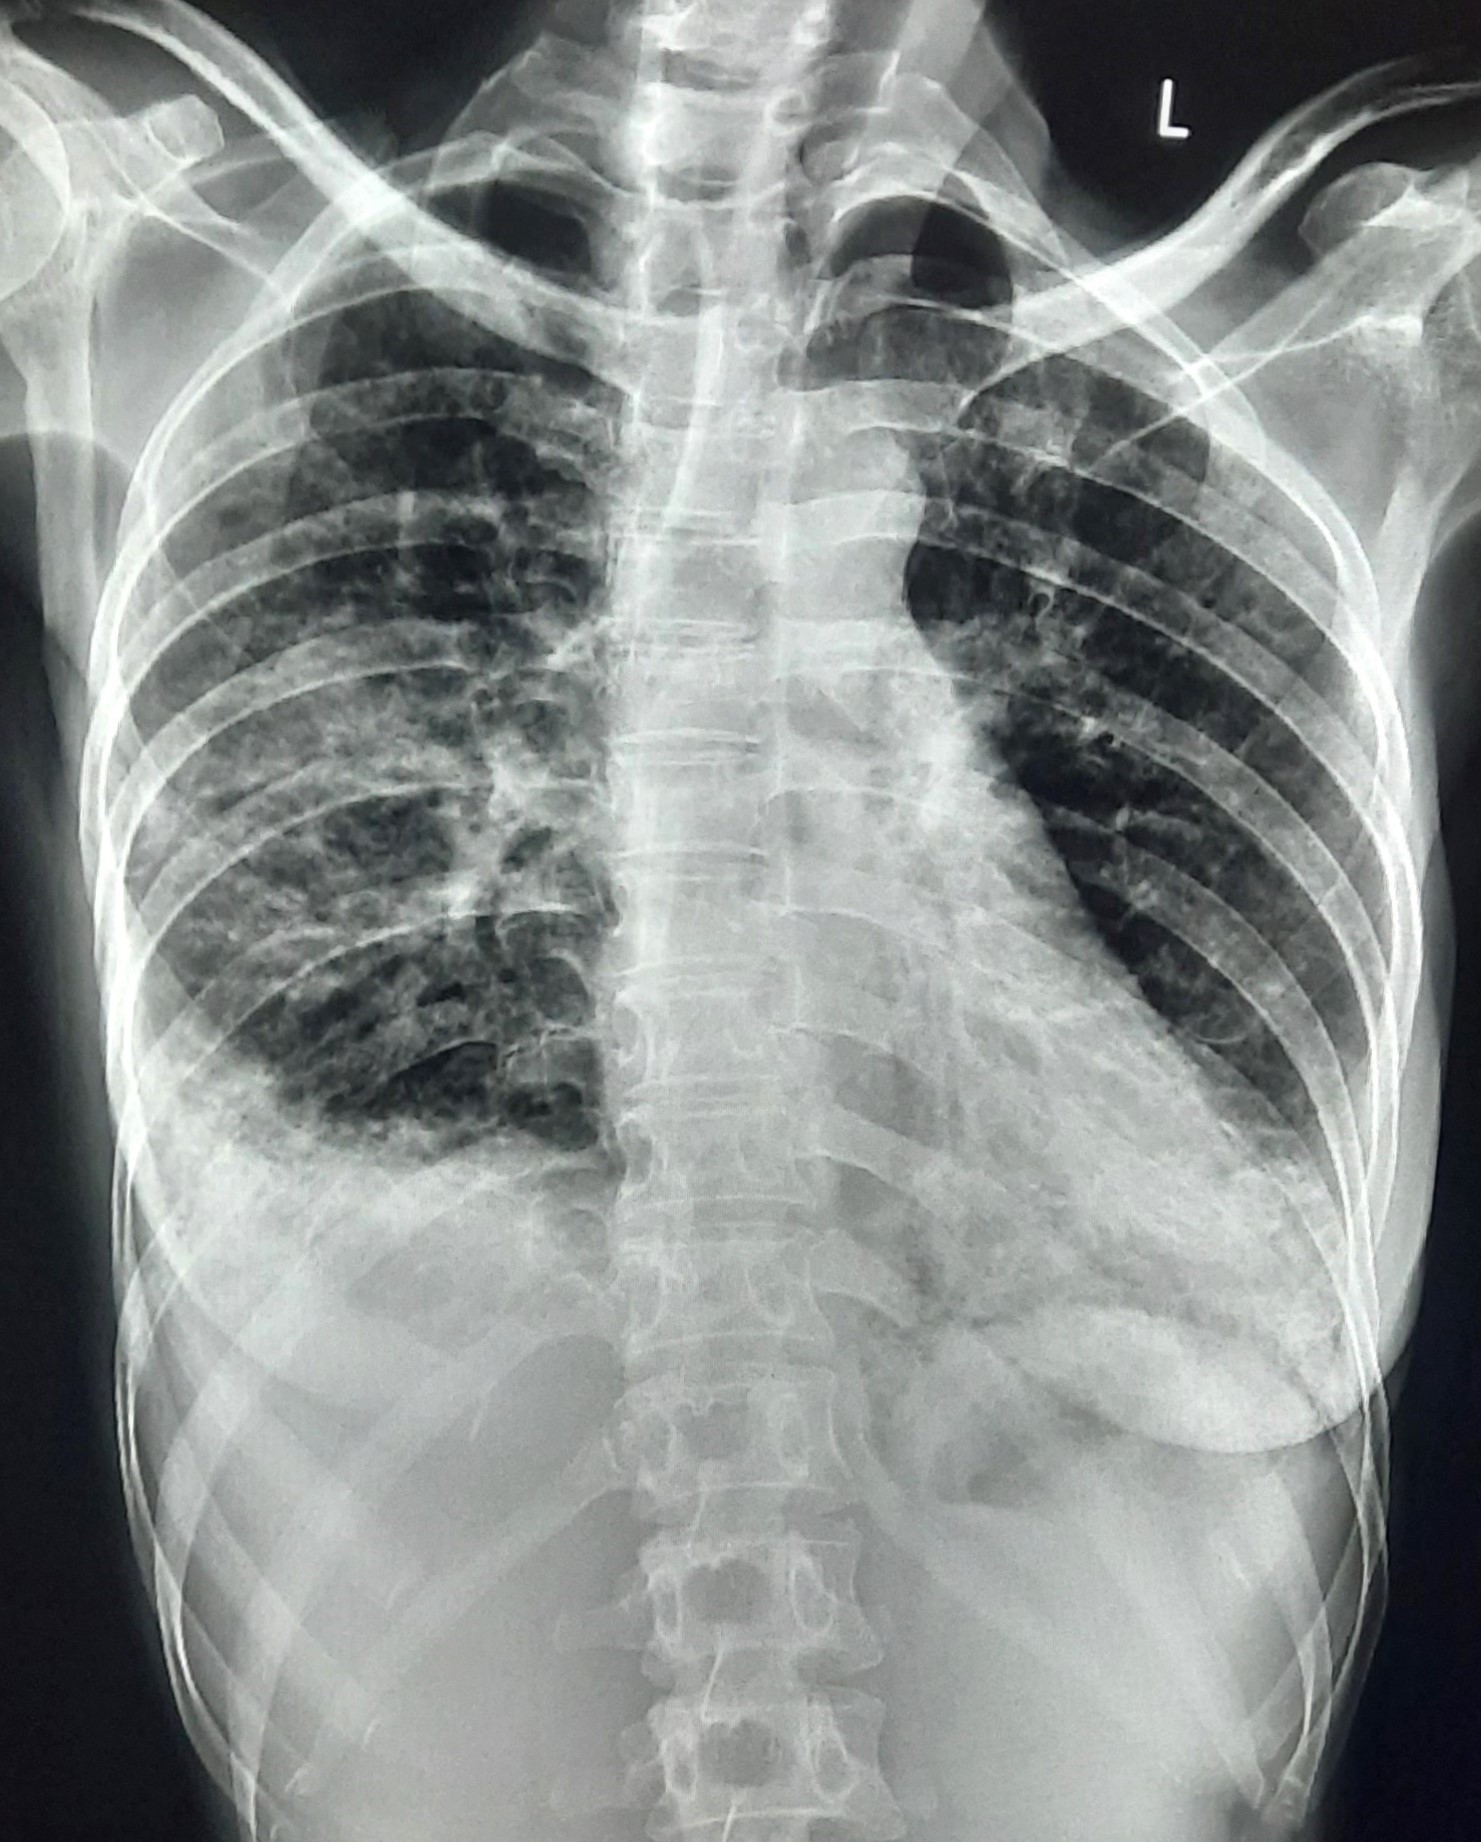

| 151 | IGGMC, Nagpur, Nagpur | P2 | 29-4321 | Chanda Bhowate | Consent taken on Paper | 42 Yrs. |

Provisional Diag : ?

Final Diag : (CxR- Right Sided Synpneumonic Effusion With Pulmonary Infiltration) |

Result awaited (Suspected TB/Non-TB) | Right CP Angle Blunting With Right Lower Zone In-Homogenous Opacity Present With Right Middle Zone/ Lower Zone Infiltration Present | Abnormality visible on x-ray |